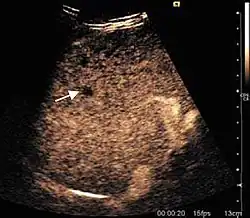

It is the most common liver tumor with a prevalence of 0.4 – 7.4%. It is generally asymptomatic but also can be associated with pain complaints or cytopenia and/or anemia when it is very bulky. It is unique or paucilocular. It can be associated with other types of benign liver tumors. Characteristic 2D ultrasound appearance is that of a very well defined lesion, with sizes of 2–3 cm or less, showing increased echogenity and, when located in contact with the diaphragm, a "mirror image" phenomenon can be seen. When palpating the liver with the transducer the hemangioma is compressible sending reverberations backwards. Doppler exploration reveals no circulatory signal due to very slow flow speed. CEUS investigation has real diagnosis value due to the typical behavior of progressive CA enhancement of the tumor from the periphery towards the center. The enhancement is slow, during several minutes, depending on the size of hemangioma and on the presence (or absence) of internal thrombosis. During late (sinusoidal) phase, if totally "filled" with CA, hemangioma appears isoechoic to the liver. Deviations from the above described behavior can occur in arterialized hemangiomas or those containing arterio-venous shunts. In these cases, differentiation from a malignant tumor is difficult and requires other imaging procedures, follow up and measurements of the tumor at short time intervals.[4]